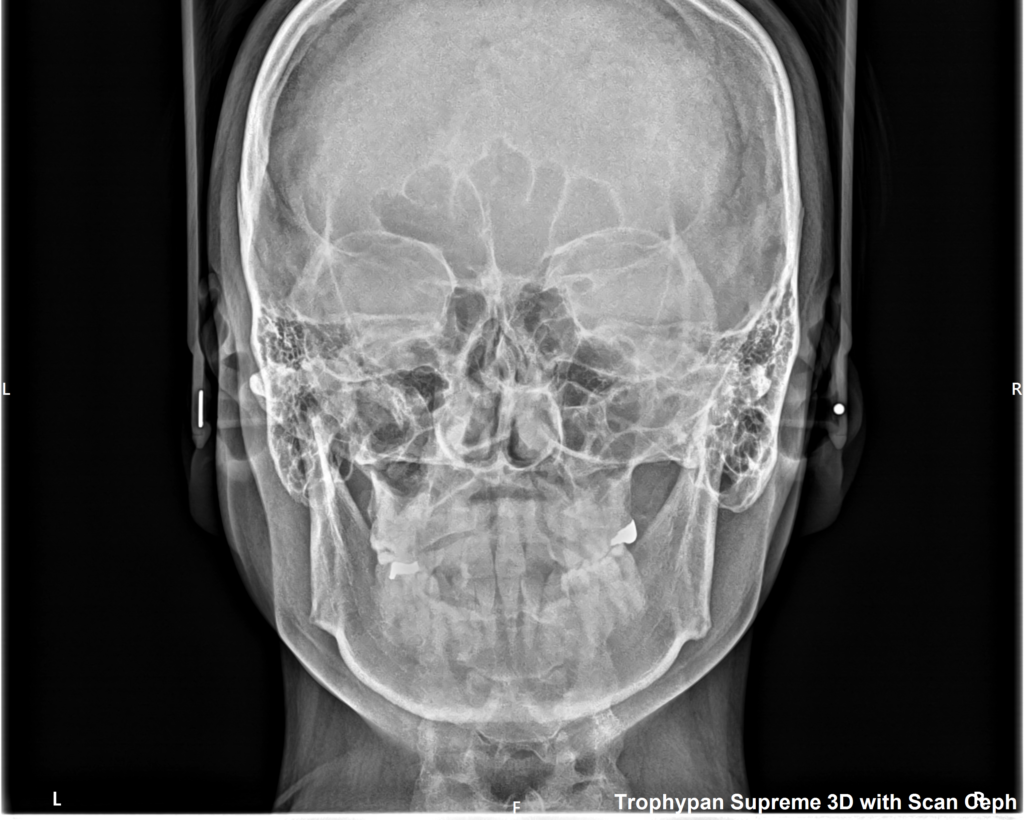

②セファロ写真

正貌写真では、正面から見た顔や顎の歪み、前歯の真ん中の位置などを確認します。